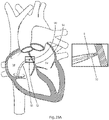

- Fig. 1 illustrates an embodiment of a medical device 20, which comprises an elongate member 6 having a proximal region 22 and a distal region 24, and an energy delivery device 15 ( Fig. 2 and, in greater detail, Fig. 5 ) associated with the distal end of device 20.

- the medical device, dilator, and sheath are introduced into the heart via the inferior vena ( Figs. 23A and 23B ).

- the curved portion 30 is defined by a radial arc and the energy delivery device 15 is directed away from cardiac structures, as shown in Fig. 23B .

- the distal region is adapted to form a 270 degree curve.